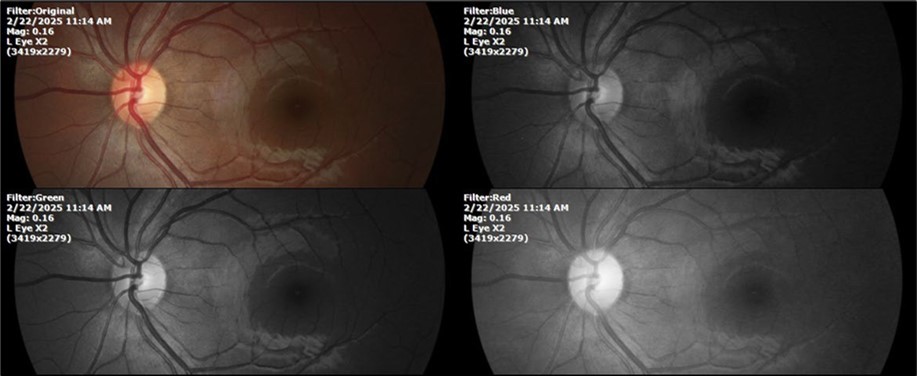

Figure 11.The photograph of the left eye does not show pathological data.

Figure 12. The photograph of the back of the eye, on the left side, shows a normal anatomy.

Figure 18.Mirror reflection of the eye on the left side, undisturbed.

Figure 19.The photograph of the fundus, on the left side, remains unaltered.

Figure 23.The mirror reflection of the left eye, without anomalies.

Figure 24.The eye that was not affected by the trauma (left side) remains in good condition.

Figure 28.The photograph of the left eye shows a specular reflection without pathology data.

Figure 29.The transparent media of the left eye does not show any alteration.

Figure 30.The anatomy of the posterior pole of the left eye is preserved, without showing pathology data.